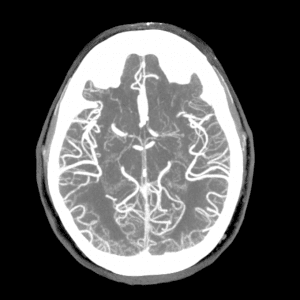

PCA infarct